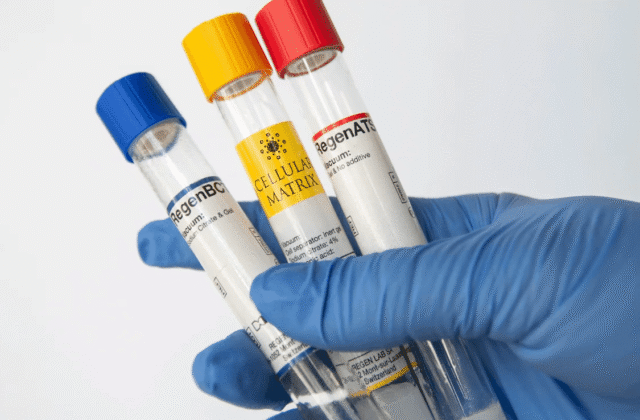

PRP-plasmateraapia

PRP-plasmateraapia – regeneratiivne meditsiin Regen Lab PRP–plasmateraapia on süstimisprotseduur naha kvaliteedi parandamiseks ja naha regenereerimiseks. Kasutatakse oma verest saadud trombotsüütiderikast…